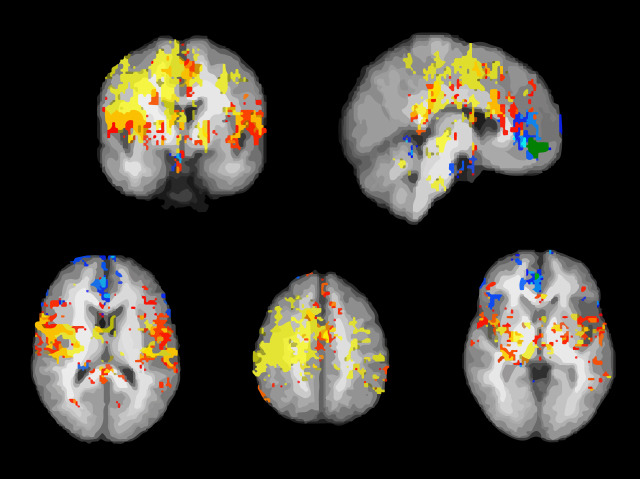

We all know how hard it is to resist scratching an itch. This natural response is part of a cycle; when you feel an itch, the sudden need to scratch can be strong. Scratching then leads to relief and to feelings of pleasure. Pictured are brain maps from functional magnetic resonance imaging (fMRI) showing the parts involved during the itch-scratch cycle. Cowhage – a hairy plant – was used to irritate the skin (activating the red-orange areas) and make the subjects scratch (activating the yellow areas). The results show that during scratching more areas of the brain are linked to pleasure, rather than relief. While relief-associated areas are known to be involved in the reward circuit, they were deactivated during scratching. Nevertheless, a feeling of reward was evoked by the drop in the intensity of the itch and the pleasure that arose from scratching – two mechanisms working together to neutralise the itch.